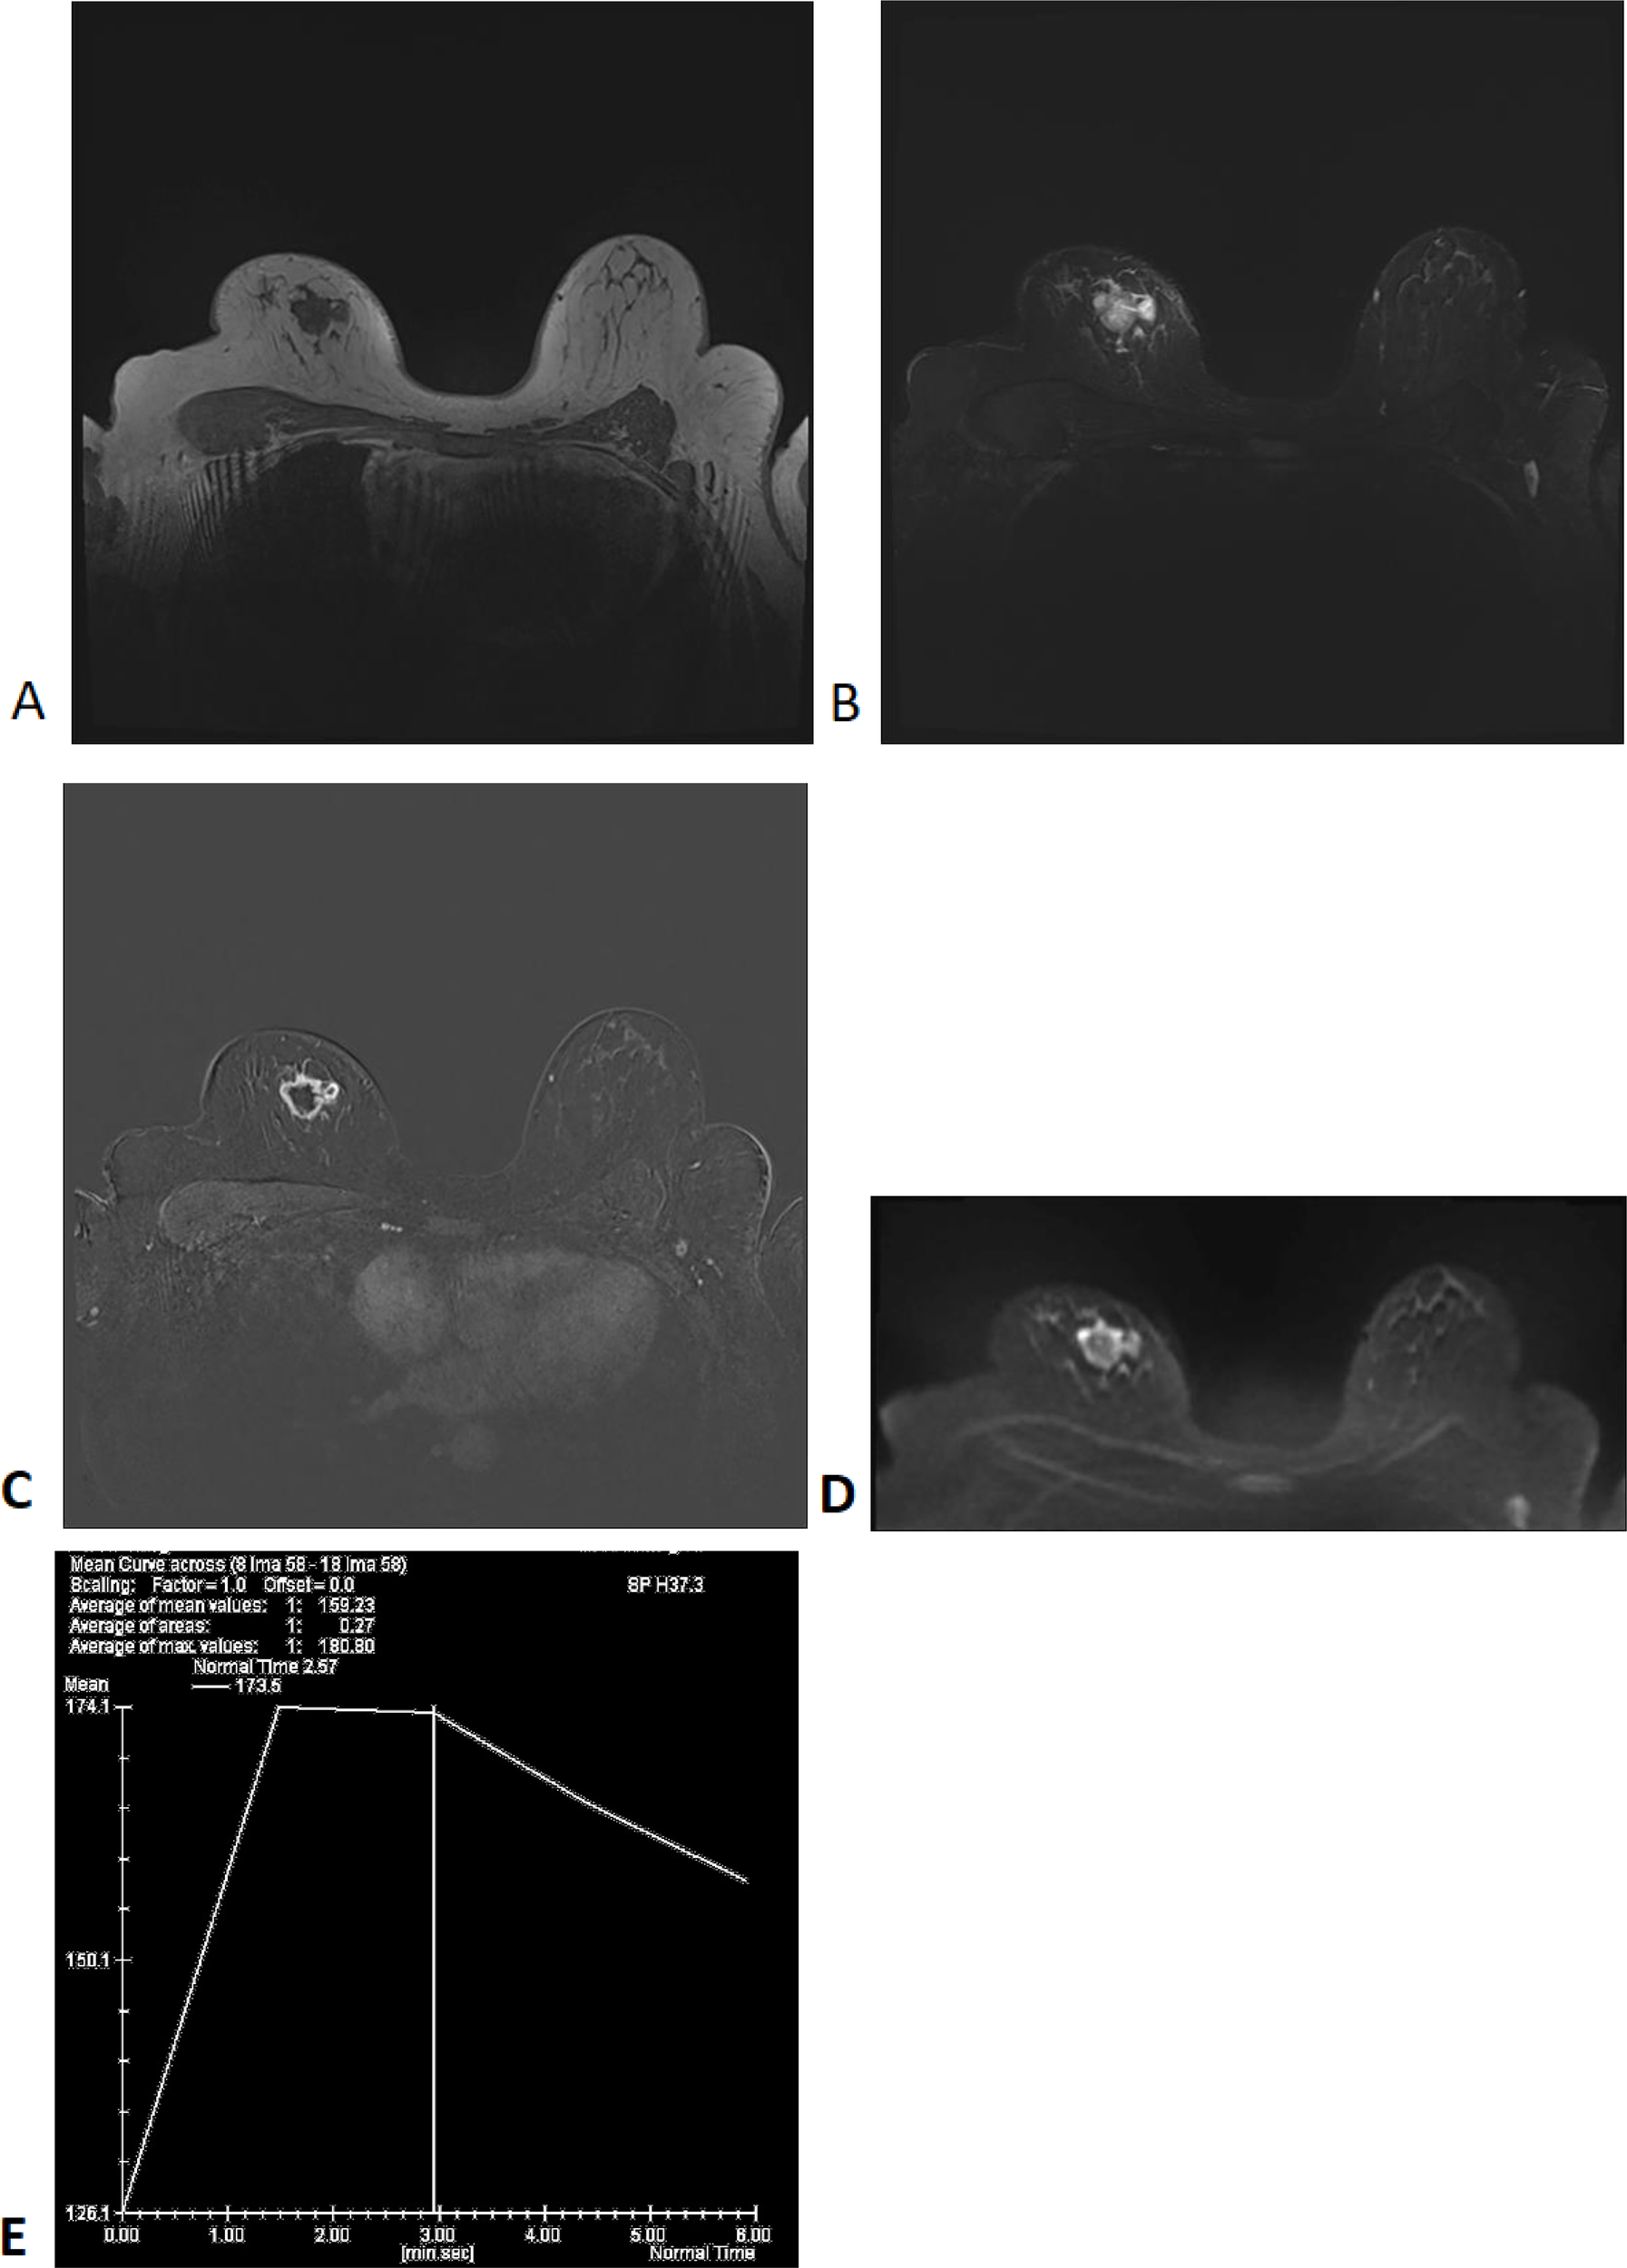

Auxiliary Examinations: Enhanced breast MRI (Figure 1) showed a lobulated mass in the right breast with a size of approximately 22×27×21 mm. T1-weighted imaging (T1WI) showed low signal intensity, while T2-weighted imaging (T2WI) demonstrated slightly increased signal intensity, with cystic changes in the central region. Diffusion-weighted imaging (DWI) revealed a thick-walled mass with high signal intensity, irregular shape, and low signal intensity in the central area. The mass was irregularly enhanced during the early phase of contrast injection, with spiculated margins. The central necrotic area showed no enhancement. The dynamic contrast-enhanced curve(DCE-Curve) showed a washout pattern, consistent with squamous metaplasia but not definitive.

Figure 1

MRI Findings: T1WI (A), T2WI (B), T1WI+Contrast (C), DWI (D), DCE-Curve (E).